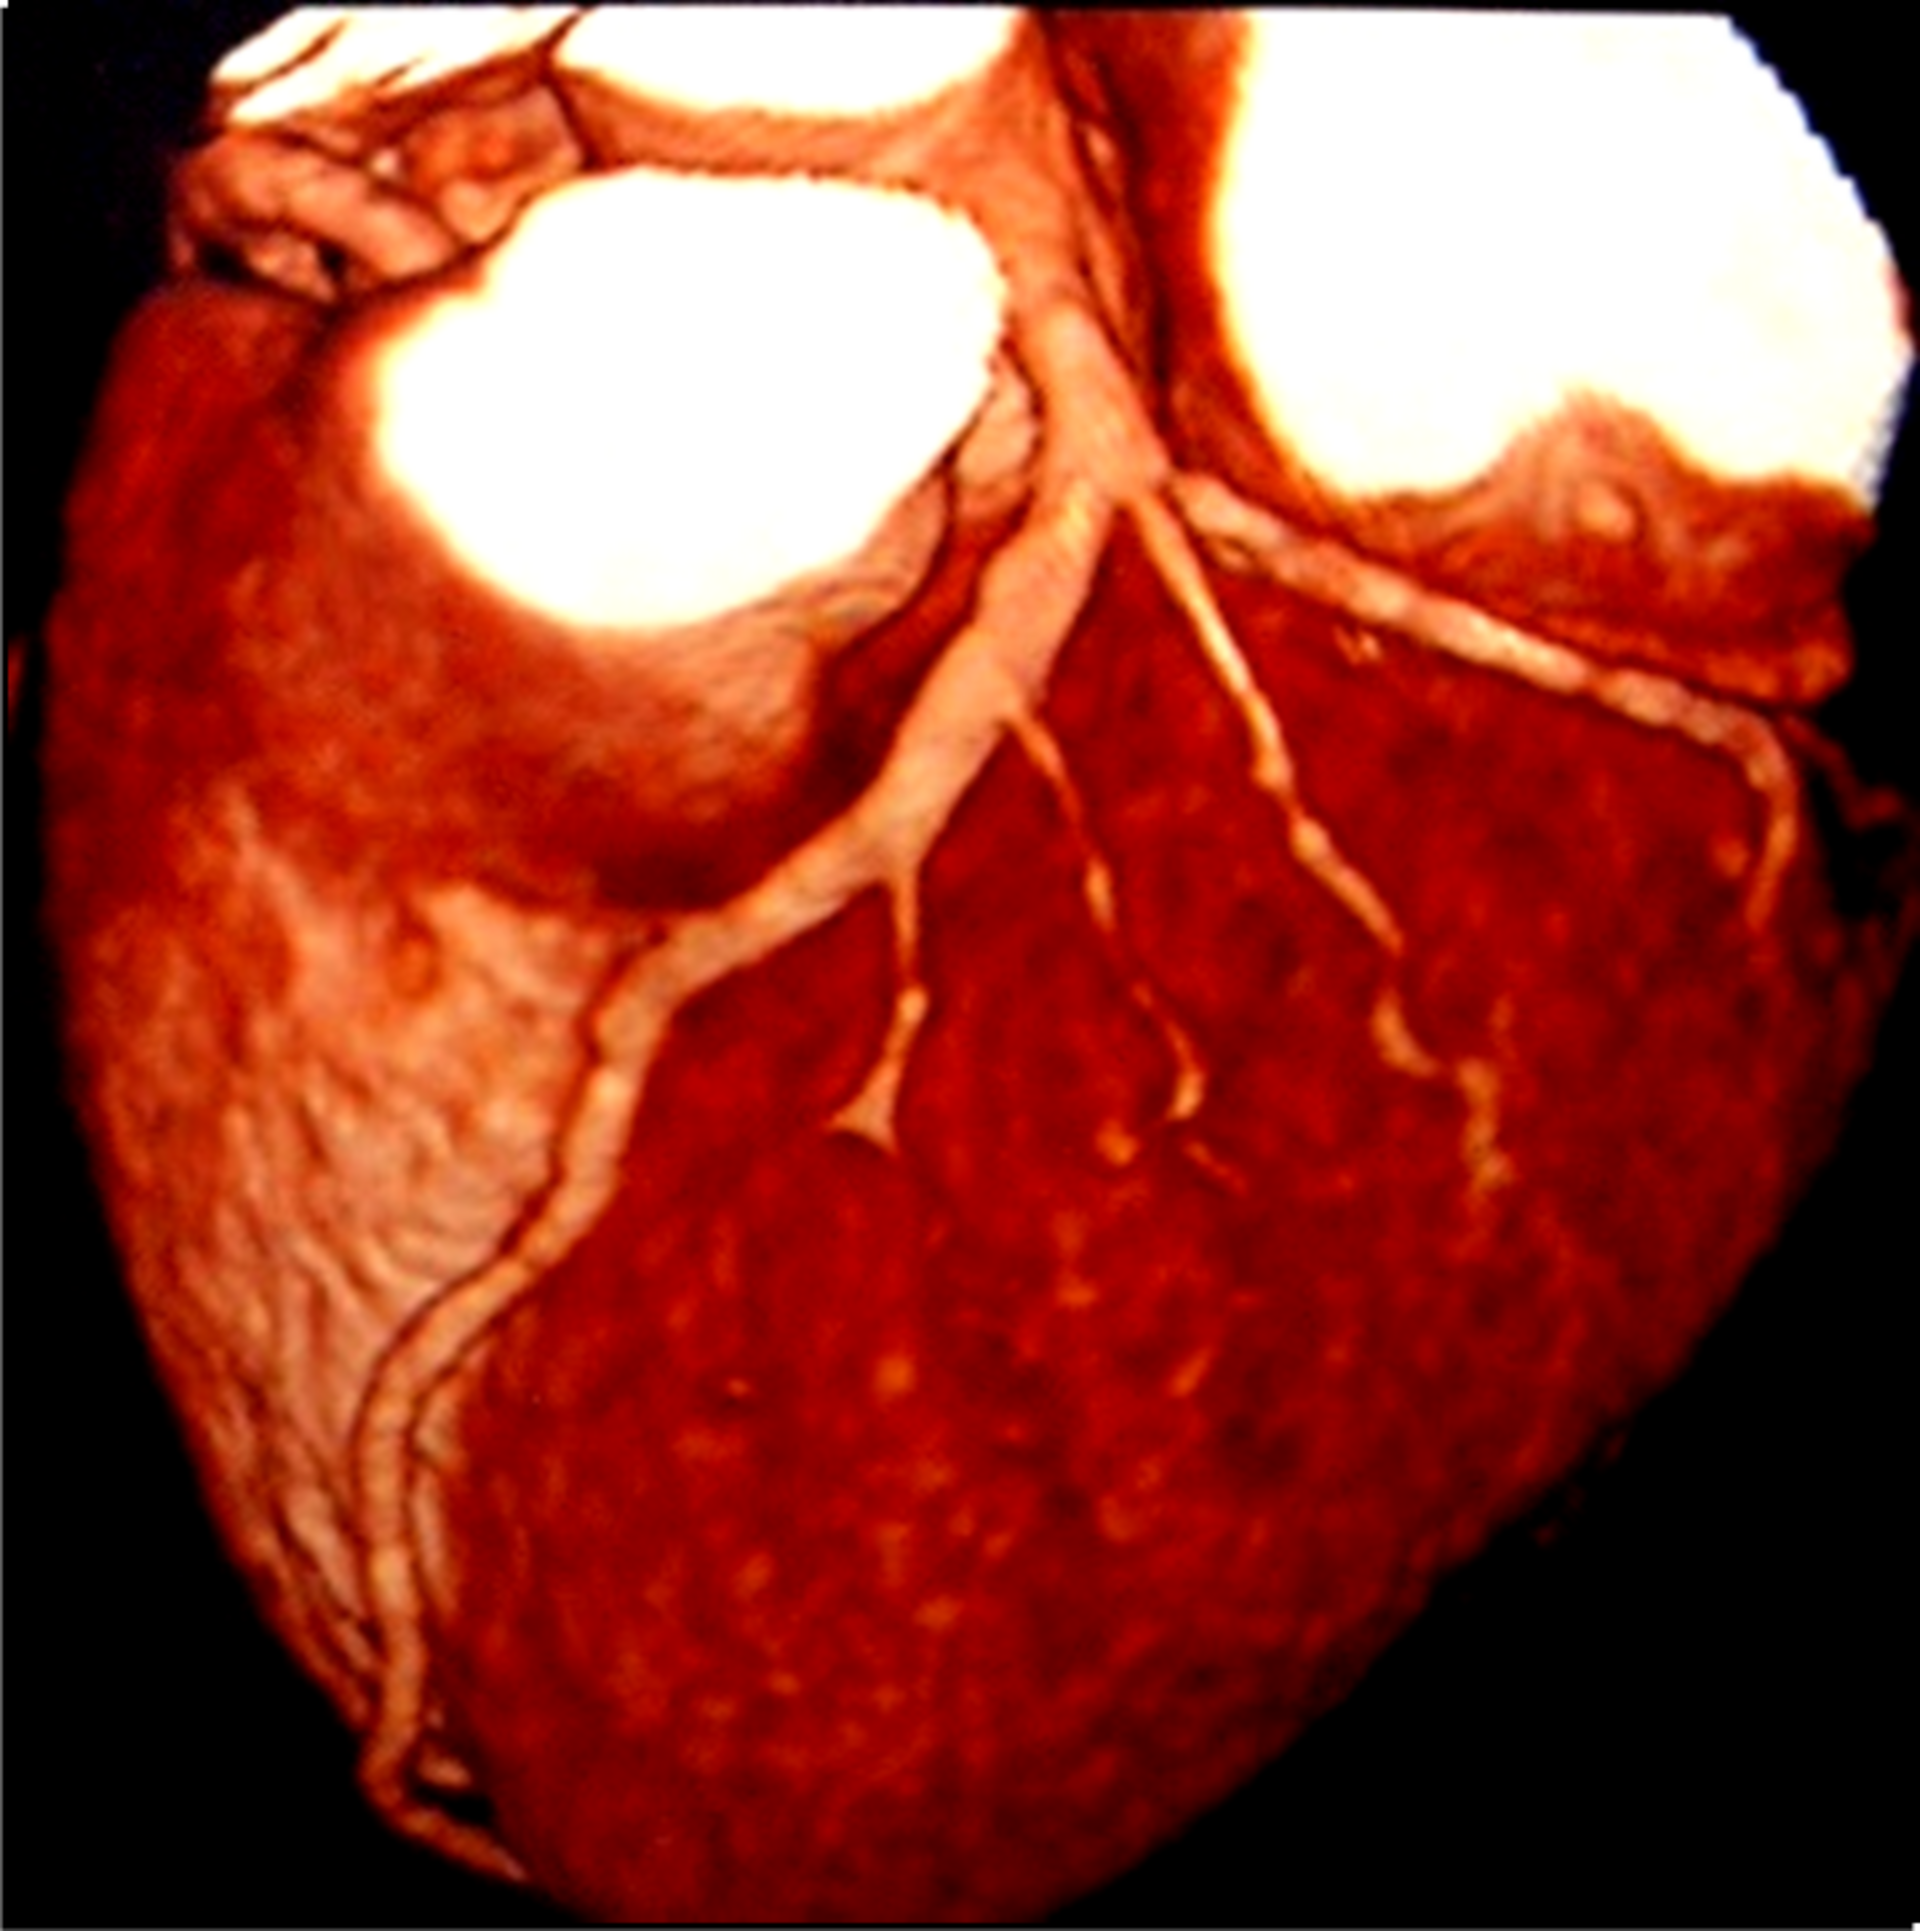

CAD In India | Dr. Hasmukh Gujar

Explosion of CAD Strikes at younger age Hits bread earner No. of Females CAD Investigations:CAD Investigations include  Stress Test Coronar...